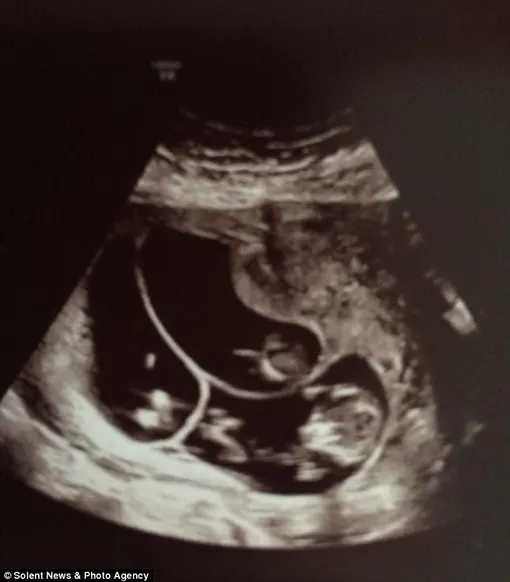

Ранний токсикоз натолкнул Шарлотту на мысль, что она может быть беременна двойней, и она оказалась отчасти права. Беременность действительно была многоплодной: УЗИ показало тройню.